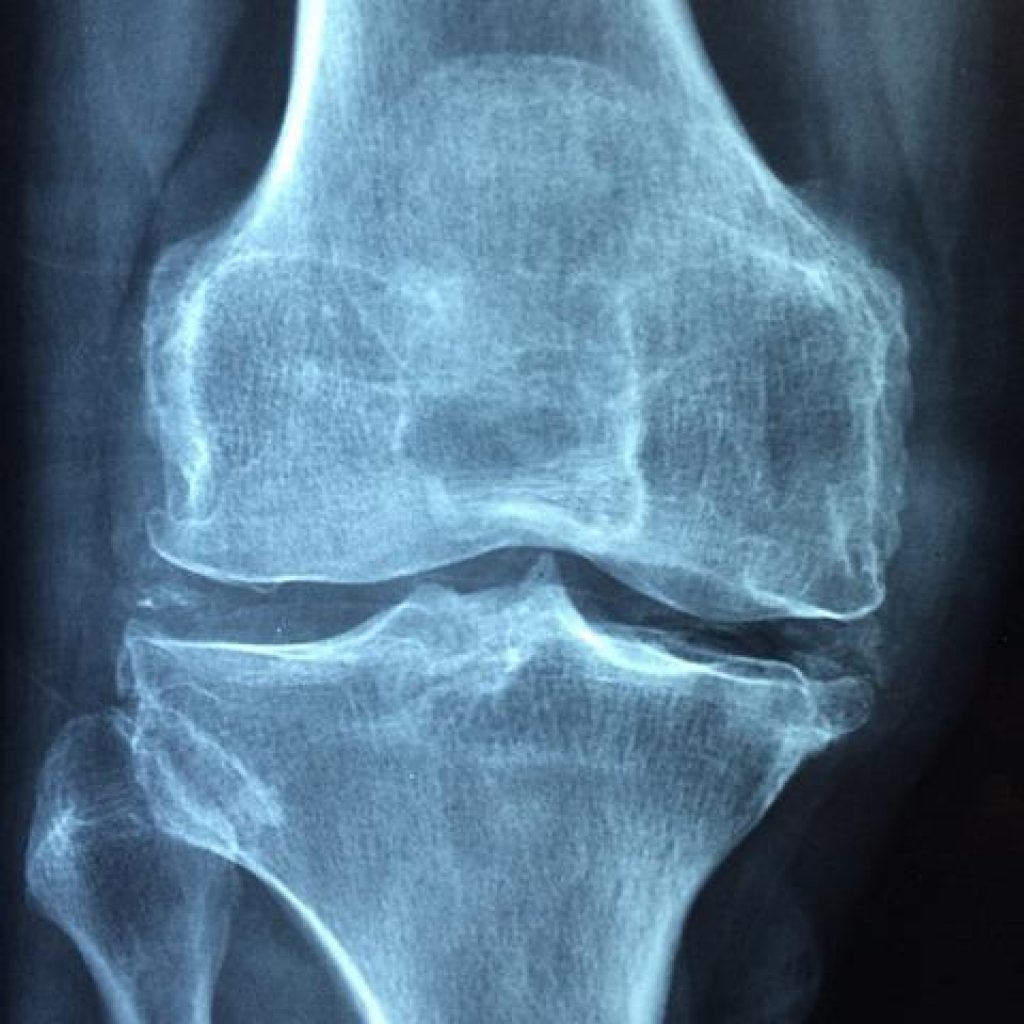

Osteoarthritis is the most common type of arthritis. It occurs when the cartilage between the bones wears away, causing pain and stiffness in the joints. Osteoarthritis can occur at any age, but it is most common in older adults. There is no cure for osteoarthritis, but there are treatments available to help reduce symptoms.

Arthritis is a term that is used to describe a group of medical conditions that cause pain, stiffness, and inflammation in the joints. There are many different types of arthritis, and the specific type that someone has can be difficult to determine. The most common symptom of arthritis is joint pain, which can range from mild to severe. Other symptoms may include joint stiffness, swelling, redness or warmth around the joint, reduced range of motion, and fatigue. Diagnosis of arthritis typically involves taking a medical history and performing a physical examination. Additional tests may be needed to determine the specific type of arthritis. Treatment for arthritis depends on the severity of symptoms and the underlying cause.